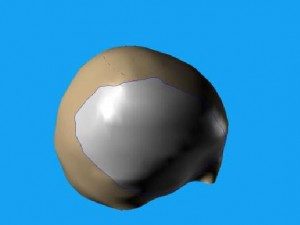

První snímky protézy